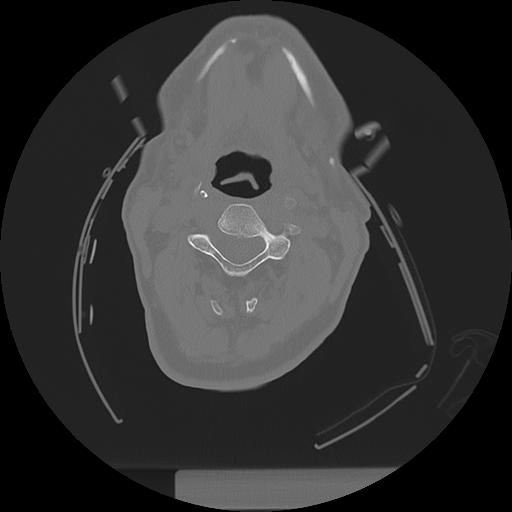

11 HUESO,,Axial,2.0,HUESO,,